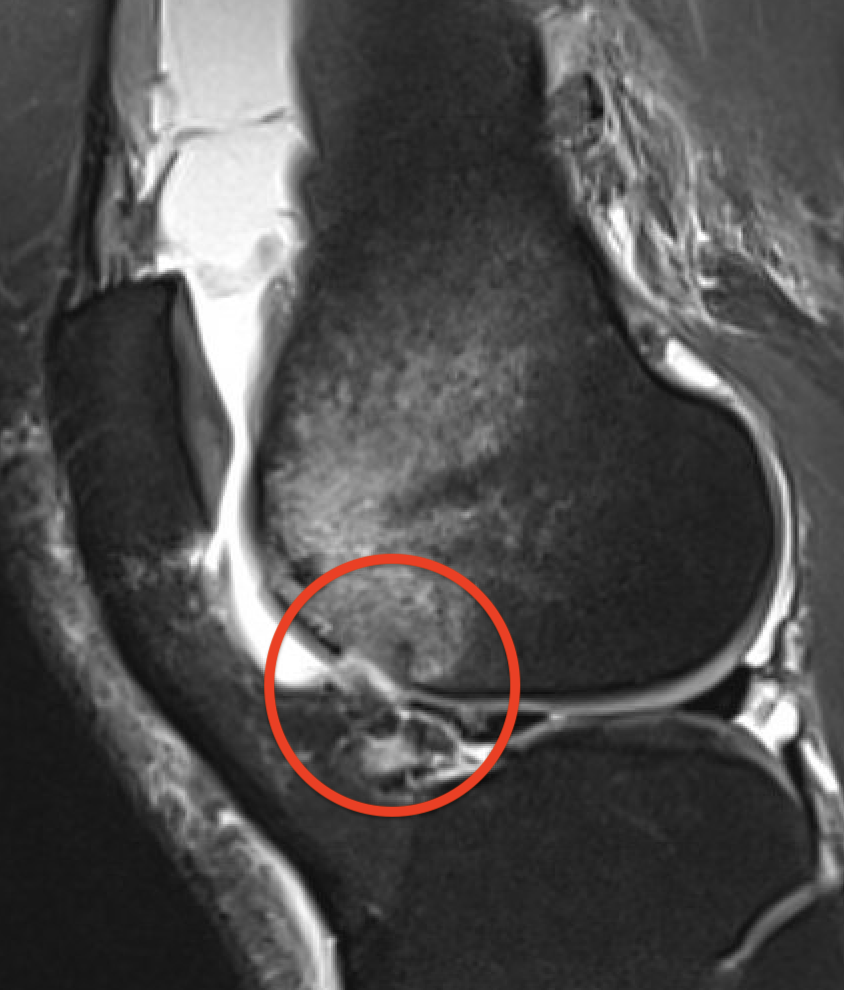

MRI

Advantage

- identify smaller chondral lesions

- identify size of osteochondral fragment better than CT

- diagnose MPFL tear location

Small chondral fracture in notch from medial facet patella, and avulsion of MPFL from patella

Large chondral fracture from medial facet of patella

Osteochondral fracture lateral femoral condyle